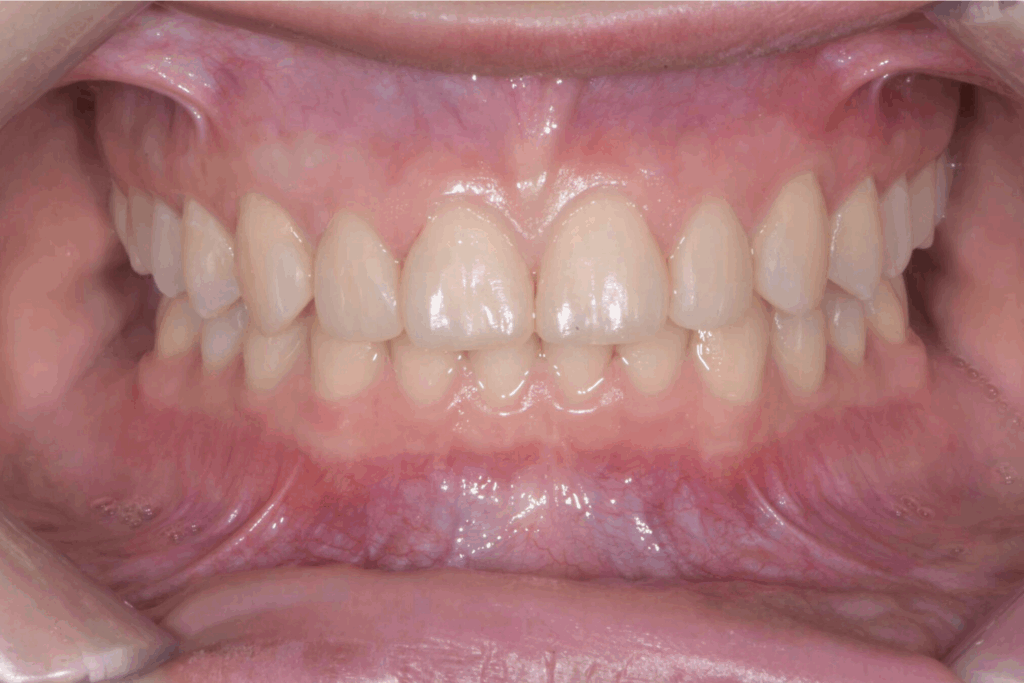

A 17 anni, una paziente si è rivolta al nostro studio con l’obiettivo di migliorare il proprio sorriso e la funzionalità masticatoria. Il caso clinico presentava una combinazione di problematiche comuni e complesse: agenesia dei settimi inferiori, incisivi superiori di piccole dimensioni e un morso profondo. Questa situazione non solo comprometteva l’estetica del sorriso, ma poteva causare problemi funzionali a lungo termine. La soluzione scelta per questa giovane paziente è stata un approccio combinato di ortodonzia moderna con allineatori trasparenti e odontoiatria estetica conservativa.

La prima fase del trattamento è stata un’analisi approfondita. Durante il check-up, abbiamo confermato la diagnosi di agenesia dei secondi molari permanenti inferiori, una condizione congenita che lascia spazi vuoti nell’arcata. Abbiamo inoltre rilevato che gli incisivi superiori erano di dimensioni ridotte rispetto al resto dei denti e che la paziente presentava un morso profondo, con gli incisivi superiori che coprivano eccessivamente quelli inferiori. Questa valutazione completa ci ha permesso di creare un piano di trattamento personalizzato e preciso, tenendo conto di tutte le problematiche presenti.

Risultato finale